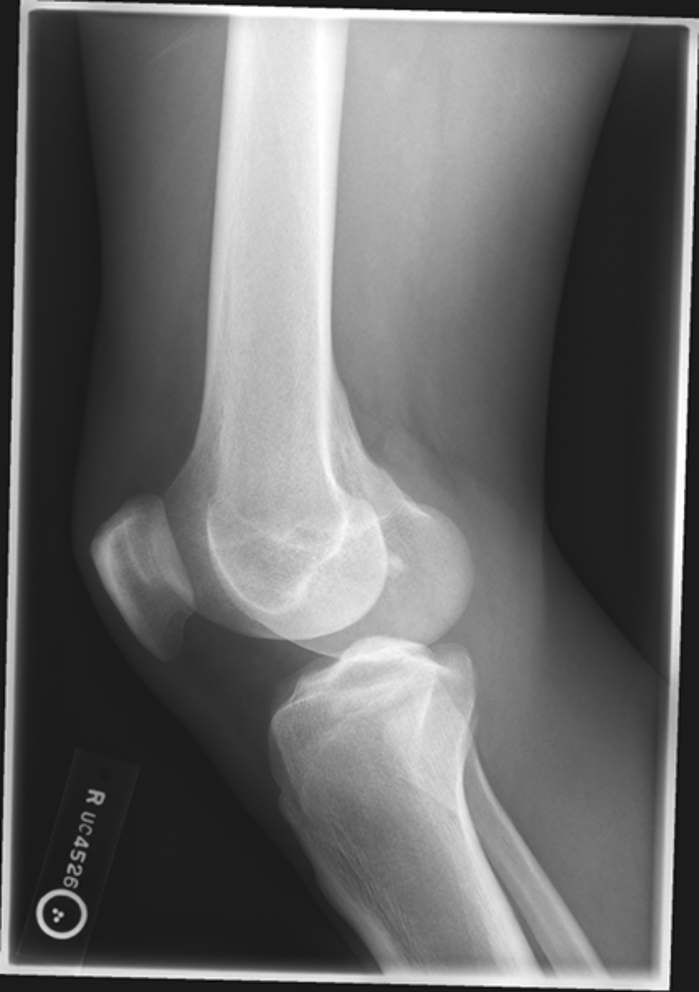

osgood schlatter

incomplete separation or avulsion of the tibial tuberosity

repeated stress to tibial tuberosity growth palte

stress leads to the tendon pulling away

what is the cause of a osgood schlatter?

pt w/ osgood schlatter

what is this image?